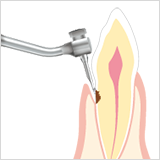

Endodonti

Kanal tedavisi temizliği

Bozuk dosyaların kaldırılması